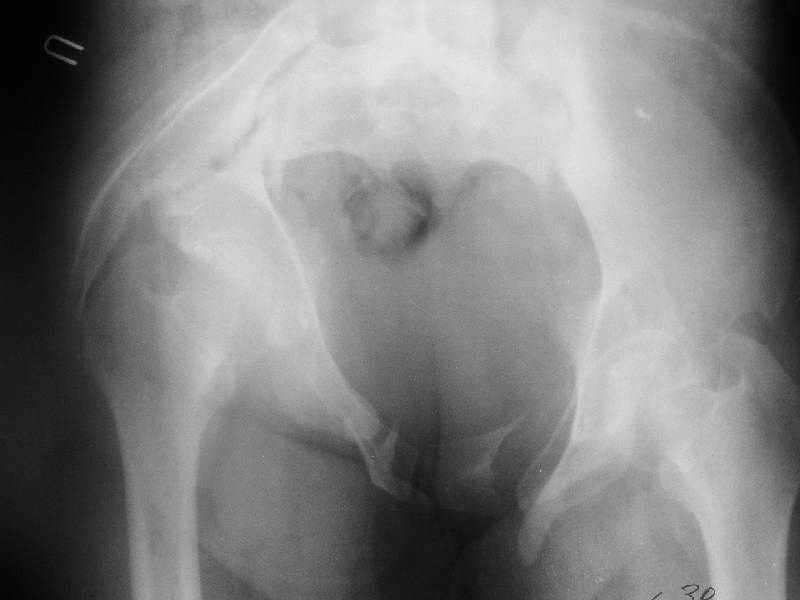

Госпитализирована больная 27 лет. Травма 1.5 года назад, сбита авто. При поступлении в местной больнице наложен фиксационный аппарат-«передняя рама». Через месяц аппарат снят из-за нагноения, разрешена ходьба с костылями. В послеоперационном периоде отмечалось нагноение забрюшинной гематомы. При обрашении к нам 3 мес назад в области промежности имелся свищ, по месту жительства выполнено иссечение свища, был гнойный затек на бедре, откуда получено до литра гноя, больная ходила с костылями.Свищ зажил 1,5 мес назад При поступлении сейчас укорочение до 5 см, ходит без дополнительной опоры, имеется выраженная хромота.Какой, по вашему, может быть оптимальная тактика оперативного лечения? Ограничиться низведением вертлужной впадины (каким доступом?), выполнить полную реконструкцию передних и задних отделов, одномоментно или поэтапно? Заранее благодарен.

По просьбам коллег отправляем снимки таза: прямая, inlet, outlet, 2 дополнительные компьютерные томограммы.